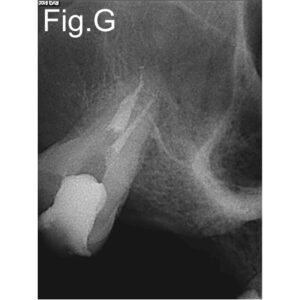

- Obturation: bioceramic sealer (bio-c sealer) and gutta-percha; warm vertical compaction.

Pre-operative periapical radiographs in different angulations or tomography favour the establishment of a correct treatment plan. In this particular case the distal buccal canal was out of its normal position making it difficult to find the entrance. Although under microscope visualization we had to follow root fusion line to find the canal. It was near the palatal. The ultrasonic tips were very important to reach the distal buccal canal at this stage. Another important factor was the common entrance of the two channels, which made difficult both a correct approach and the obturation. Clinicians should be aware of this anatomical conformation before starting the treatment. A straight irrigation protocol is imperative in this these cases. Only experience and knowledge can avoid errors that may be irreversible.